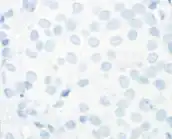

Micrographs showing each score:[46]

0

0 -

1+

1+ -

2+

2+ -

3+

3+